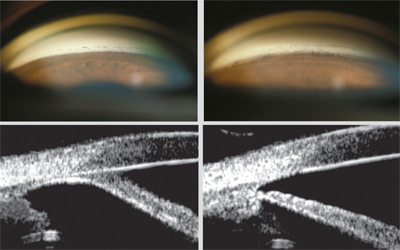

1. 각막함입술, Corneal indentation

이는 외래에서 시행할수 있는 가장 간단한 처치입니다.

각막의 중심부를 눌러서, 전방수를 주변부로 이동시켜, 주변부 전방을 인위적으로 깊게 만드는 방법입니다.

전방각 검사를 시행하는 전방각 검사용 특수렌즈인

전방각경 (gonioscopy lens) 중에서 각막의 직경보다 더 작은 전방각경으로

각막의 중심부를 누르는 방법을 사용합니다.

이는 전방각경검사를 통해 주변부 전방각을 관찰도 하면서,

폐쇄된 전방각을 열기도 할수 있는 처치 두가지가 동시에 가능합니다.

그 외에도 누운상태에서 면봉처럼 끝이 부드러운 기구로 각막의 중심부를 직접 누르는 방법도 가능합니다.